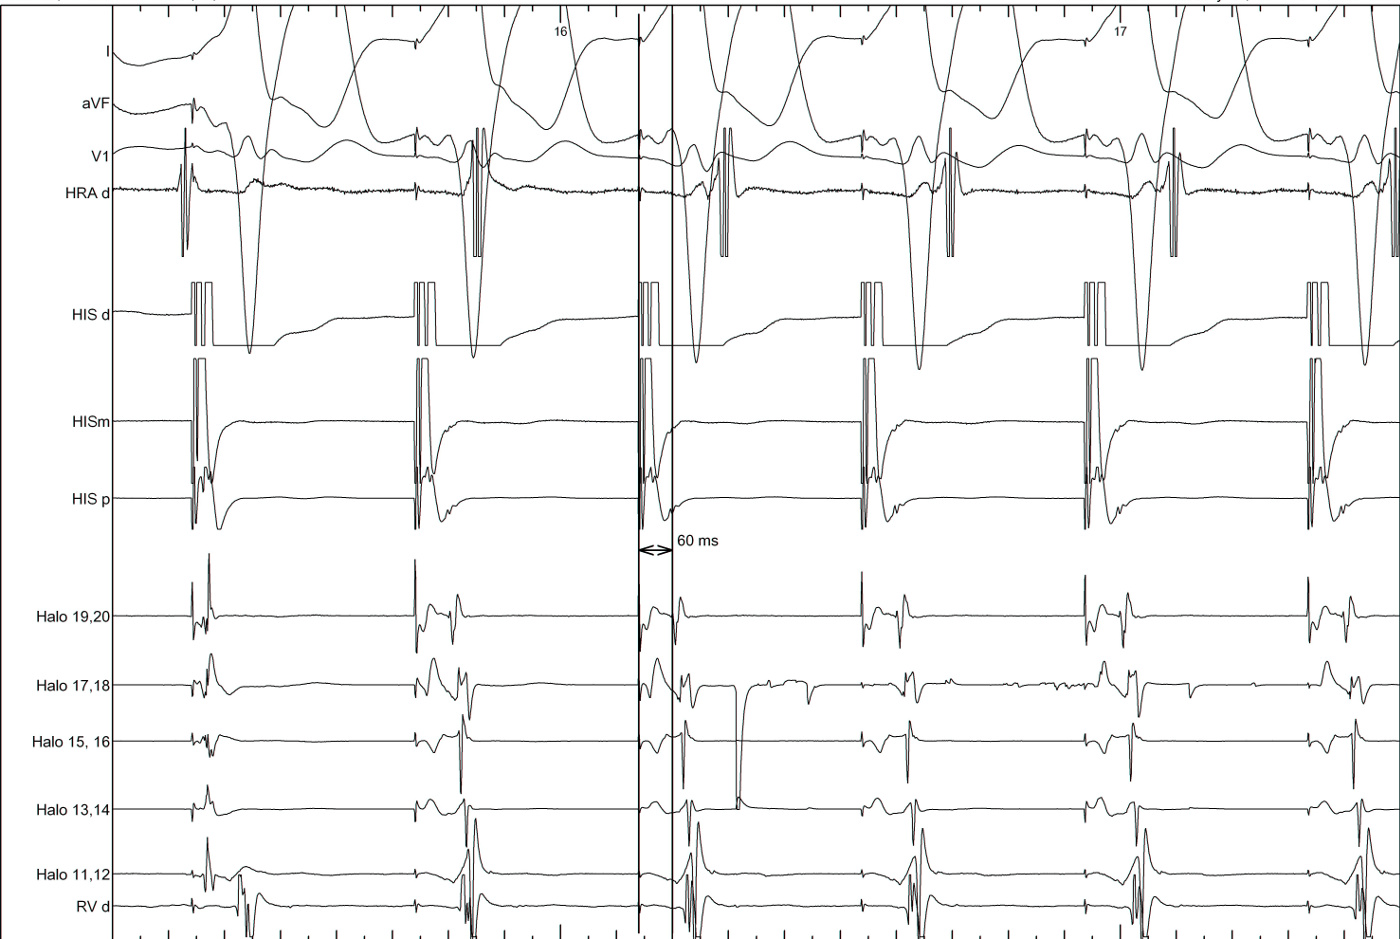

Beginning of entrainment can give a clue

entrainment_onset.jpg

• Atrial acceleration in transition zone

• A entrainment before H entrainment